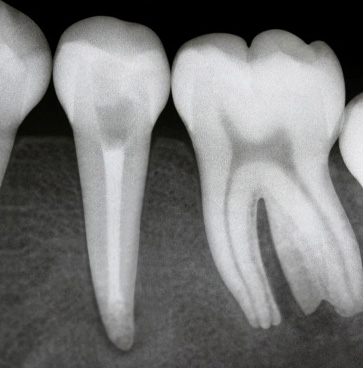

A 12-year-old female patient came to the Dental Hospital of the Federal University of Uberlândia (HO/UFU) reporting a spontaneous, diffuse, intermittent, long-lasting pain exacerbated by chewing plus cold and hot stimuli. Tooth 35 had a coronary access performed in a private dental practice six months earlier. Radiographically, unsatisfactory coronary access, thickening of the periodontal ligament, a diffuse periapical lesion and the presence of an open apex were observed (Figure 1A).

Figure 1A. Radiographic aspects after removal of the provisional restoration.